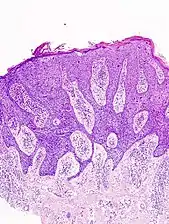

In situ disease

Bowen's disease is essentially equivalent to and used interchangeably with cSCC in situ, when not having invaded through the basement membrane.[12] Depending on source, it is classified as precancerous[13] or cSCC in situ (technically cancerous but non-invasive).[47][48] In cSCC in situ (Bowen's disease), atypical squamous cells proliferate through the whole thickness of the epidermis.[12] The entire tumor is confined to the epidermis and does not invade into the dermis.[12] The cells are often highly atypical under the microscope, and may in fact look more unusual than the cells of some invasive squamous-cell carcinomas.[12]

- cSCC in situ, high magnification, demonstrating an intact basement membrane.[12]